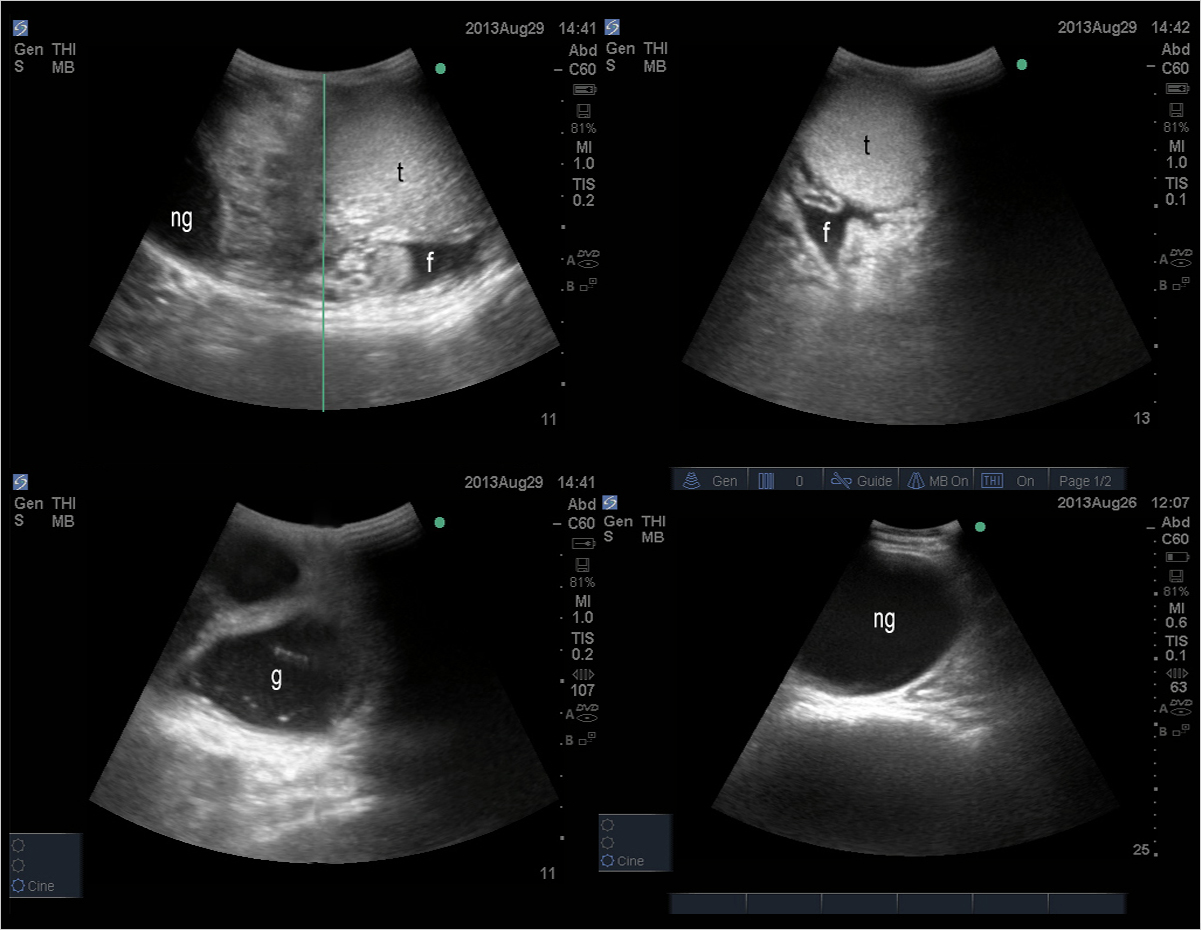

Source: www.researchgate.net